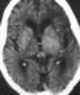

Primary brain neoplasm

A brain tumor occurs when abnormal cells form within the brain. There are two main types of tumors: cancerous (malignant) tumors and benign (non-cancerous) tumors. [Source: Wikipedia ]